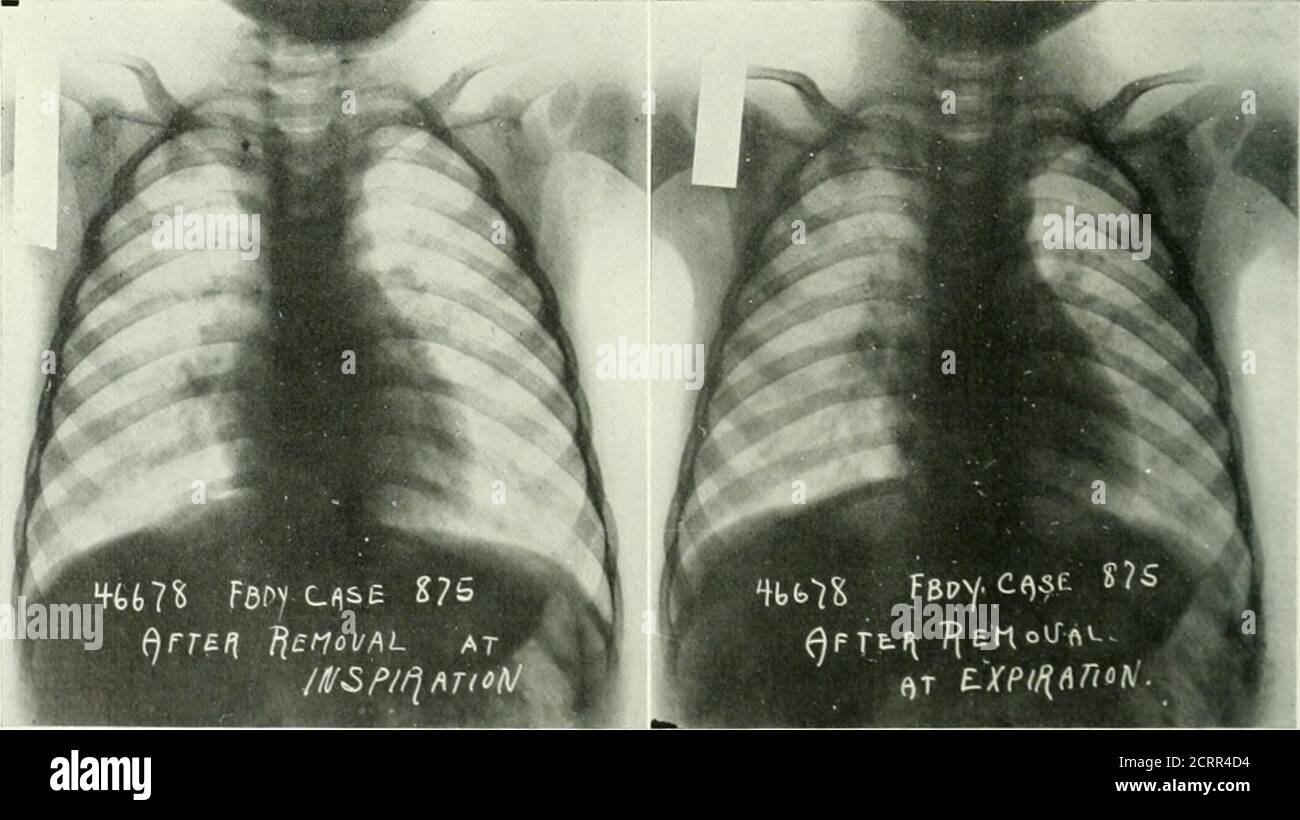

Pediatric Foreign Body. Chest Xray, Annotated. JETem 2018 JETem Chest X Ray Inspiration And Expiration Image quality should always be assessed because it may not be possible to answer the clinical question if the image is inadequate. The phase of respiration has a profound effect on the appearance of several structures on the chest radiograph (see case 2 for inspiration and expiration. Case discussion this case highlights the importance of optimal technique: If the image. Chest X Ray Inspiration And Expiration.